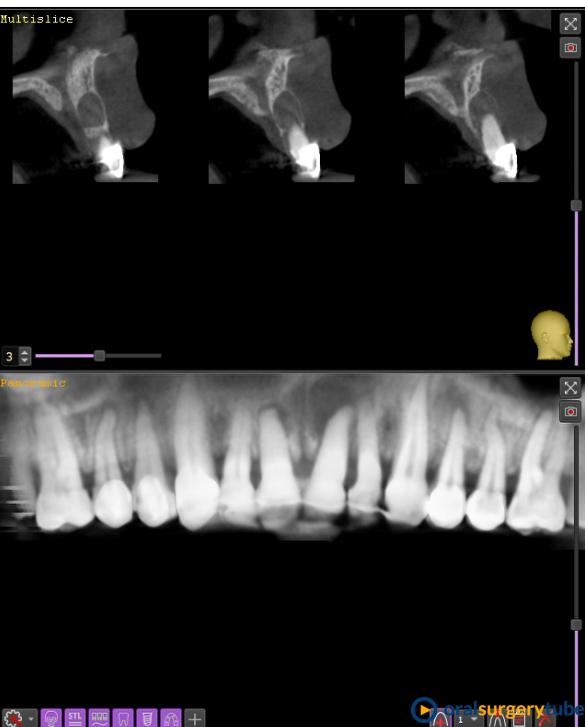

Paciente mujer joven, fumadora y de higiene regular. Con periodontitis moderada estabilizada pero con mal mantenimiento y con un proceso muy avanzado en el 21. Se le realiza en el mismo acto la extracción, legrado y lavado profuso, fresado y colocación guiada del implante con torque de 20N . Y después se regenera el aveolo con mix de autólogo de rama rascado con un micross y Bioss collagen y un injerto de tuberosidad en vestibular. No se hace carga inmediata por la baja estabilidad, se coloca y tapón de cicatrización y periacryl para sellar. Buscando un tratamiento similar (salvando mis infinitas limitaciones y distancias) a los protocolos de actuación de dos gigantes como Mesquita (implanteperio) y/o el de David González y su articulo de 3 Layers para alveolos sin tabla. Me decido por esta opción ya que todo lo que fuese levantar un colgajo sería al 100% un desastre estético y no estoy capacitado para un bloque mixto de tuberosidad ósea y blanda. Quizá haya fallado mi diagnostico o mi técnica.

Aparentemente la cicatrización es buena, asintomático y con buen aspecto. Pero en el control a 4 meses veo muchísima reabsorción de mi regeneración en vestíbulo. Sería por el potencial osteoclástico en ese lecho? o por no poner una capa de reabsorción lenta en la parte más externa?... en unos días probaré a ver si no me quedo con el implante en la mano.